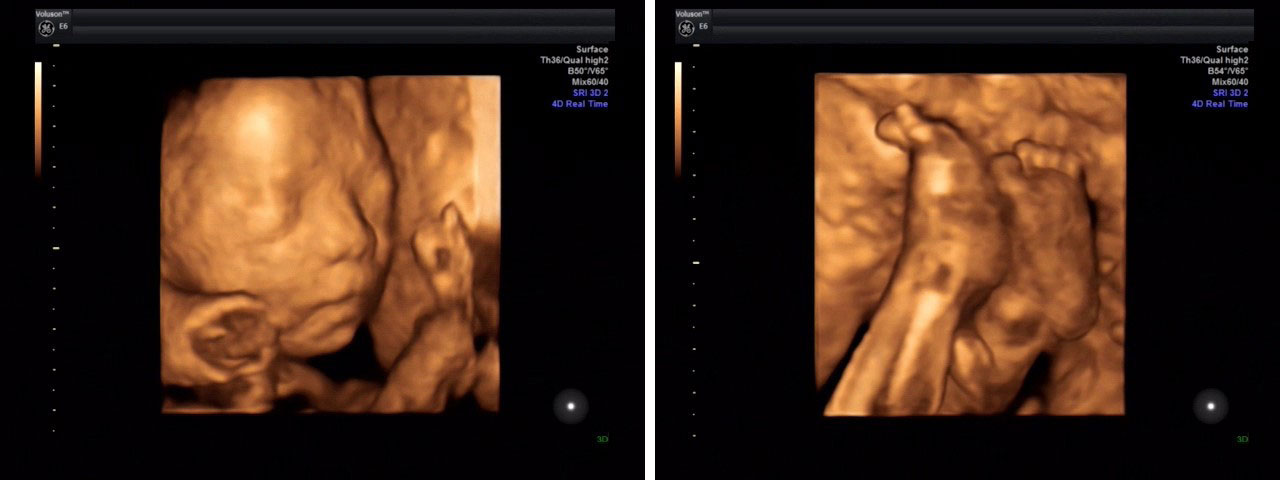

优势②→画面更清晰:我院引入的全新升级美国GE四维彩超是目前福州高端的四维彩超设备能360°立体展示胎儿各器官的发育情况,应用于胎儿产前筛查及缺陷儿终极诊断,并完整记录胎儿宫内高清动态。